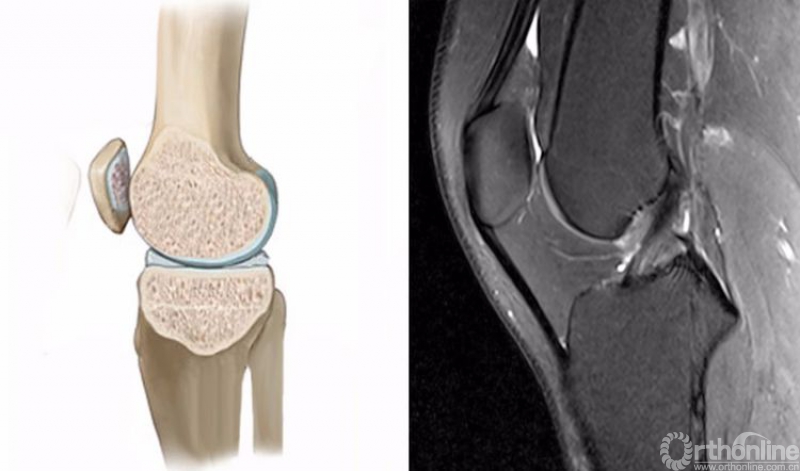

正常的膝关节进行MRI扫描时,不管任何一个序列,其骨髓信号一般T1WI呈均匀一致的灰色,T2WI及STIR呈均匀一致的黑色。

2.膝关节矢状位的正常MRI图像